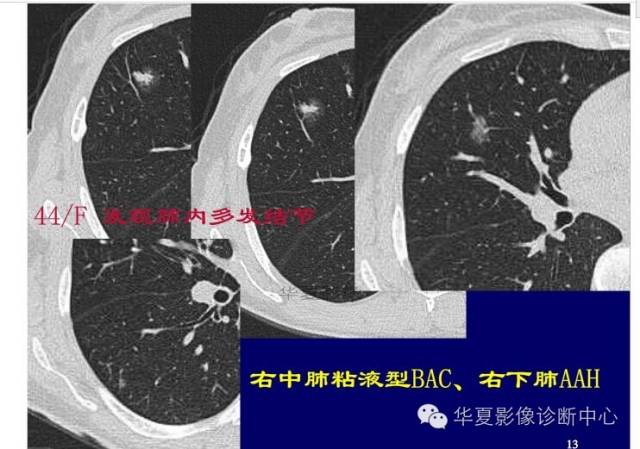

第一步:判断是否GGO

第二步:判断是否肿瘤

第三步:看边缘及内部征象

磨玻璃结节良恶性影像分析策略 混合型,边界清楚、分叶征,考虑肺癌